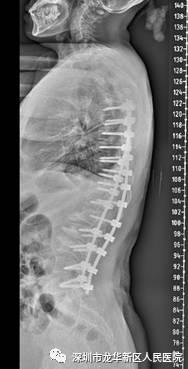

深圳市龙华区人民医院脊柱外科张昊团队、麻醉科张亚军团队,联手医疗卫生“三名工程”项目第四军医大学西京医院罗卓荆教授骨科团队成员李新奎教授,成功开展了一例高难度重度特发性脊柱侧凸畸形矫形手术。

经详细询问病史、体格检查及辅助检查,腰椎向左侧凸,左侧腰背部膨隆,右侧凹陷,Cobb角达75度,剃刀背畸形,即腰前屈时两侧背部不对称,医生明确诊断向女士为脊柱侧凸畸形,决定为治疗患者疾病决定行脊柱侧凸畸形矫形手术。

为充分保证手术的成功实施,手术前,医院完善患者各项检验检查,充分评估患者手术风险,全面开展术前宣教,积极做好术前准备工作。手术由深圳市龙华区人民医院脊柱外科张昊主任主刀,深圳市卫生医疗“三名工程”项目引进的第四军医大学西京医院罗卓荆骨科团队成员李新奎教授指导。这台手术历时10余小时后顺利完成。

手术让向女士重获新生腰椎侧弯获得完美矫形,身体麻木的症状也明显缓解,疼痛更是完全消失。术后身高还增长了4厘米,后续将进一步接受康复治疗。